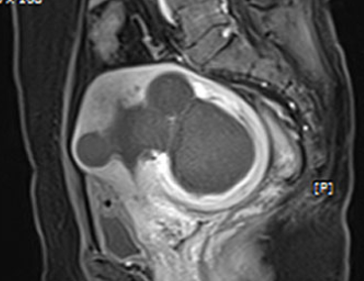

자궁근종 치료 사례

• 시술 전

시술 후